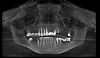

Irs61 Опубликовано 27 февраля, 2013 Поделиться Опубликовано 27 февраля, 2013 (изменено) Здравствуйте, уважаемые врачи!Вот такая нерадостная картинка. КТ - GALILEOS, у меня получилось сделать только скриншоты.Последний раз протезировалась в 2002 году, до этого где-то в 1993-м. Слетели 2 моста: слева верх (с 24 по 27, 25 и 26 не было) и справа низ.Сейчас удалили 24, пролечили заново 27, 45, 47. На верхней челюсти слева отсутствует 3 зуба подряд.Я планирую 3 этапа имплантации: в начале сделать левую часть: достаточно будет 2 имланта вверху и 1 внизу + синус-лифтинг верх?2 этап: справа верх и низ, верх скорее всего опять синус? Там я пока не понимаю сколько имплантов, скорее всего 2 вверху+1 внизу3 этап: верхние центральные зубы - там 2 импланта+синус-лифтинг обязательно с какими-то временными коронками, чтобы можно было ходить на работу и т.д. и т.п.Плюс еще ставить коронки на свои зубы по мере снятия мостов и пролечивания всех каналов Правильно ли я думаю или как лучше? Нужно ли будет наращивание костной ткани внизу?Вообщем, помогите, пожалуйста составить понятный план имплантации с протезированием, чтобы на консультации я могла уже более правильные и нужные вопросы задавать. Изменено 3 марта, 2013 пользователем Большой Зеленый Ссылка на комментарий

Irs61 Опубликовано 4 марта, 2013 Автор Поделиться Опубликовано 4 марта, 2013 Пока разбиралась со скриншотами появились новые вопросы. Сняли мост внизу слева: 37 зуб на удаление. Врач советует слева вверху - 2 имплантата с синус-лифтингом, внизу один на месте 36. Кости вроде бы хватает для одномоментного проведения синус-лифтинга и имплантации. Мосты справа и по центру снимать и перелечить, там еще 12 проблемный с каким-то штифтом, и на их места снова ставить мосты. Одиночные имплантаты между депульпирированными зубами он не советует из-за возможности воспалительных процессов. Слева имплантацию советует до шестерок. Протезирование через полгода после имплантации одновременно всех зубов.Врач мне нравится, все подробно объясняет, и внутренне я ему доверяю, но хотелось бы услышать еще мнения других профессионалов, а потом принимать решение. Все-таки мероприятие затратное и материально и физически, хотелось бы получить хороший результат на долгий отрезок времени. Потом лечение некоторых зубов превышает по цене установку имплантатов, вот и думаешь может проще удалить их, а то получится просто перенесение процедуры на несколько лет. Ссылка на комментарий